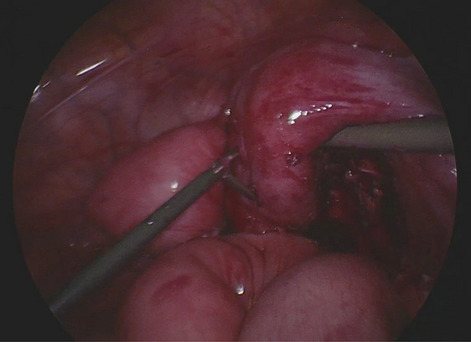

There is now consensus that where possible, minimally invasive surgery should be offered to patients for improved clinical outcomes. However, universal adoption and penetration of laparoscopy into healthcare systems has been challenging over the past two decades. Whilst there are certain procedures which are ubiquitously carried out with laparoscopy, for example, cholecystectomy, there is much variability in other seemingly more complex procedures. One of the main drivers of this has been the relative rudimentary, straight laparoscopic instruments which limit accessibility and manoeuvrability in confined spaces such as the pelvis and thorax. Consequently. in some countries where resources exist there has been a push towards robotics where advanced instrumentation allows an increased range of movements and thereby making difficult anatomy more accessible.

Until now there have been early attempts at producing advanced laparoscopic systems but these have been cumbersome and limited in their engineering. We present a revolutionary new advanced laparoscopic instrumentation system called ArtiSential. The ArtiSential instruments include bipolar forceps, Maryland dissector, monopolar spatula, monopolar hook, needle holder, with more on the way. They allow a wide range of articulating movement through 7 degrees of freedom that can mimic the dexterity of robotic platforms (Fig. 1). Traditional laparoscopic instruments have limited range of movements but these instruments allow for complex articulating movements in different planes which can be further exploited around the fulcrum of the port. This additional articulation means that there is better access to difficult part of anatomy. Furthermore, there is tactile feedback on the instrument handset which is lightweight and disposable.

Our initial series of cases include pelvic colorectal surgery and demonstrate the advantages of articulating instruments (Fig. 2). Further, we demonstrate that there is a learning curve to these instruments to maximise their benefit during complex procedures. We suggest adopting the formal training programme which includes a period of dry lab training before embarking on clinical cases so that surgeons may truly benefit from these advanced instruments. This also allows for safer introduction of new technology.

Advanced laparoscopic instruments such as ArtiSential should be used to make challenging aspects of laparoscopic surgery more accessible. These are not substitute for all straight instruments but best used to maintain precision during difficult manoeuvres in combination with traditional instruments.